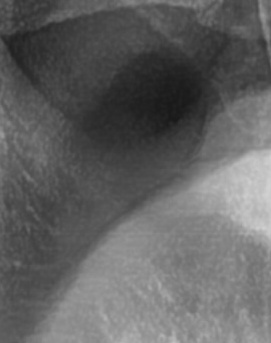

어금니 뒤 잇몸 부음의 문제는 사랑니가 원인이 되는 경우도 많은데 사랑니는 특히 현대인들의 경우 제대로 나오지 못하고 매복되는 경우가 많으며 완전히 나오지 않은 사랑니는 잇몸 속에서 자라면서 주변 잇몸을 자극할 수 있고, 일부만 노출되면 음식물이 끼면서 염증이 생기기도 하며 특히 어금니 뒤쪽 잇몸이 붓고 지속적으로 불편함을 느낀다면 사랑니로 인한 염증을 의심해 볼 수 있어요. 사랑니로 인한 문제의 경우 단순한 소염제나 구강 세정제로 해결되지 않고, 사랑니를 발치해야 잇몸 염증이 해결되는 경우가 많이 있어요

결론적으로는 통증이 심하거나 염증이 오래 지속되는 경우에는 치과를 방문해서 정확한 진단을 받는 것이 중요한데 단순한 잇몸 염증이라면 치석 제거와 항생제 치료로 호전될 수 있지만, 치주염이 진행된 경우라면 보다 적극적인 치료가 필요할 수 있어요. 만약 사랑니로 인해 잇몸이 자꾸 붓는다면 사랑니 발치를 고려해야 하겠고 사랑니가 완전히 매복되어 있다면 수술적인 방법으로 제거해야 할 수도 있어요. 특히 반복적으로 붓는다면 사랑니 검사를 받아보거나, 치과에서 정밀 검진을 통해 치주 상태를 확인하는 것이 필요하다는 점에서 어금니 근처의 잇몸이 반복적으로 불편하다면 꼭 치과를 찾아보시길 바라고 있어요